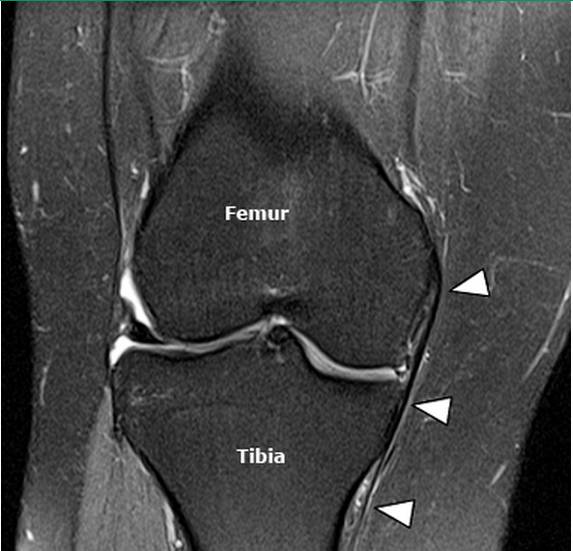

内侧副韧带损伤时MRI的典型表现包括韧带深浅两层间的滑膜囊肿胀、皮下软组织肿胀、内侧副韧带撕裂与周围血肿。韧带纤维的损伤可从单纯的排列紊乱到完全撕裂(图5~图8)。其他MRI表现有关节腔积血、股骨外侧髁或胫骨平台挫伤、半月板损伤、其他韧带损伤、以及股骨内侧髁的部分撕脱骨折(极为少见)。MRI的冠状位图像可很好地观察内侧副韧带及后内侧角。

图5,正常内侧副韧带的MRI图像。各序列低信号“条带”影,“条带”从股骨内侧髁延伸至胫骨平台下约7cm处。

图6,内侧副韧带I级损伤。肉眼观内侧副韧带完整,但仍可见高亮信号覆盖(箭头区域),此为撕裂的韧带纤维所导致的水肿。I级损伤中,水肿只在浅层可见,内侧副韧带粗细正常,紧贴骨皮质。

图7,内侧副韧带II级损伤。韧带部分撕裂,内侧副韧带深层浅层纤维均可见高信号水肿影(箭头所示)。

图8,内侧副韧带III级损伤。内侧副韧带完全横行撕裂,箭头所示位置为正常黑色韧带纤维局部断裂区域,此区域血肿水肿包绕内侧副韧带。韧带纤维撕裂部位不平整。需注意区分高等级的II级撕裂与III级撕裂。